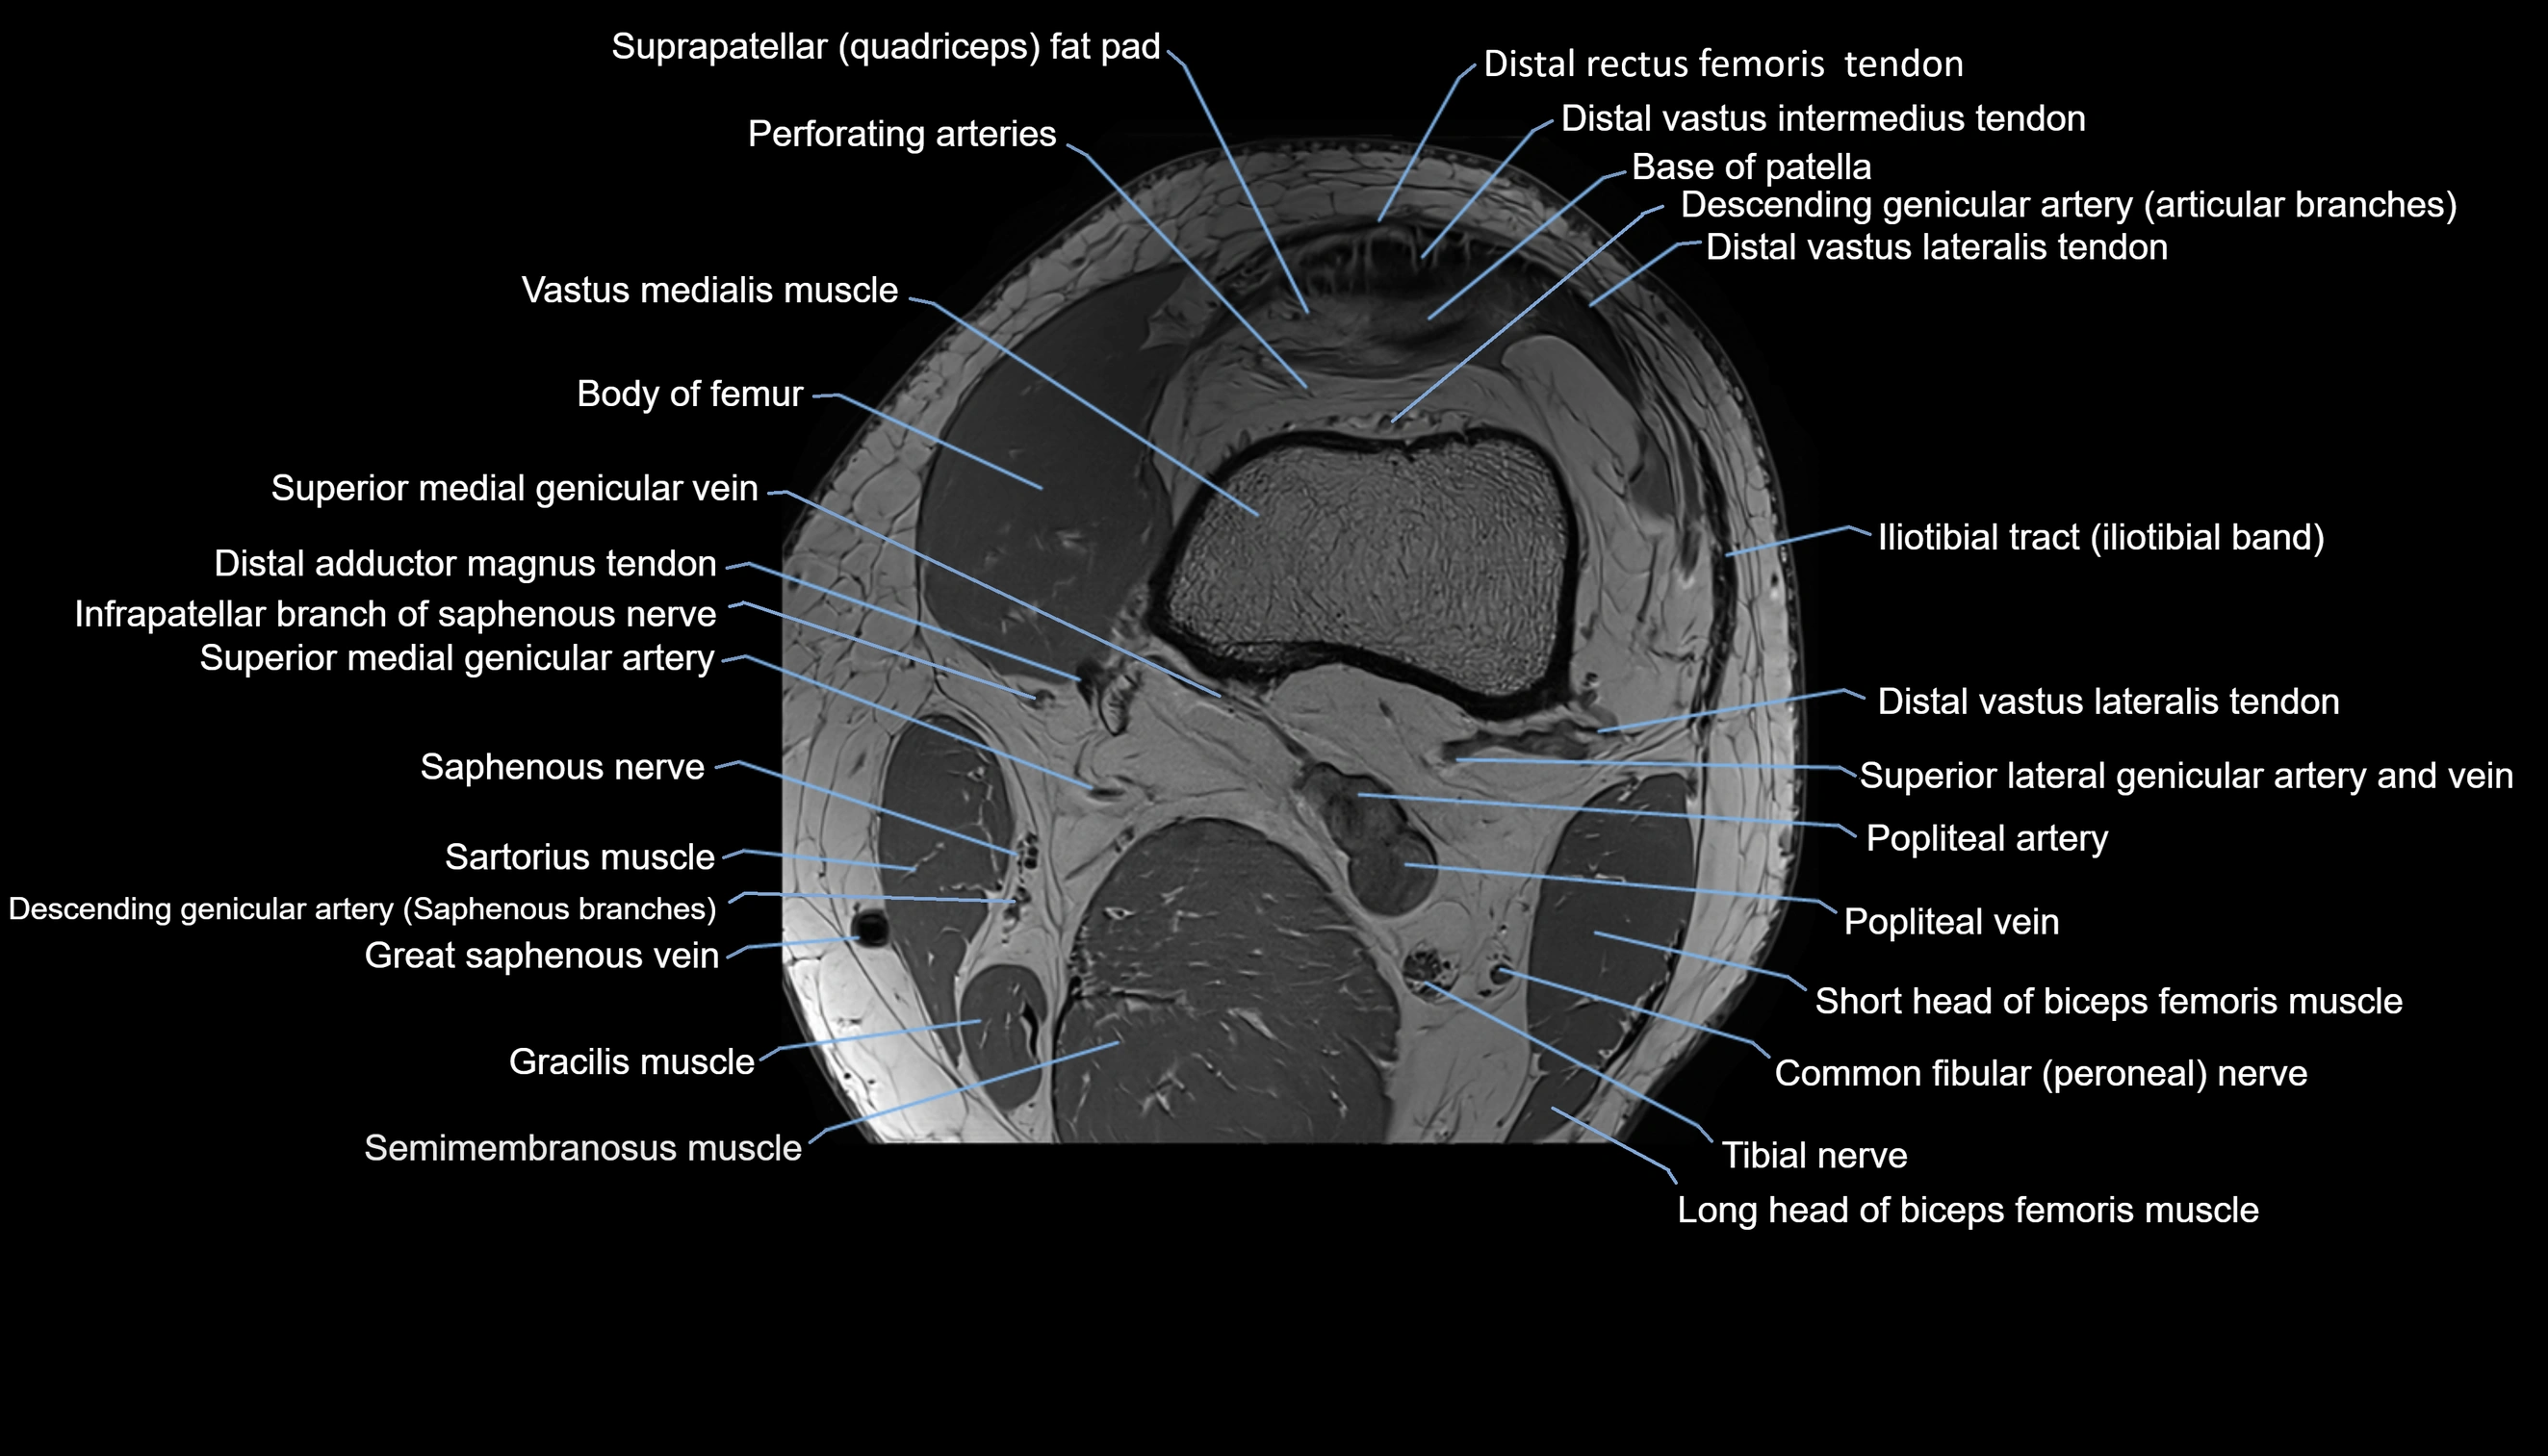

- Perforating Arteries (Knee joint)

- Popliteal artery

- Popliteal vein

- Saphenous nerve

- Sartorius muscle

- Semimembranosus muscle

- Superior medial genicular vein

- Superior medial genicular artery

- Tibial nerve